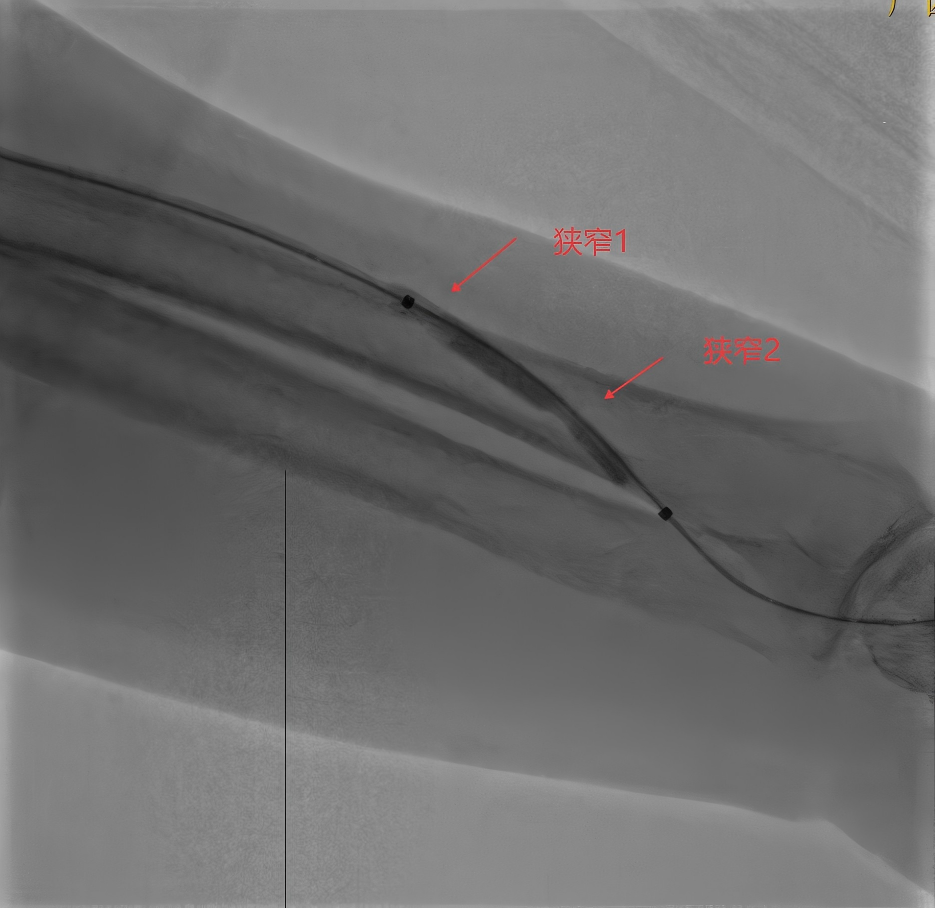

球囊抵达吻合口上方静脉狭窄段

球囊缓慢加压出现两个腰